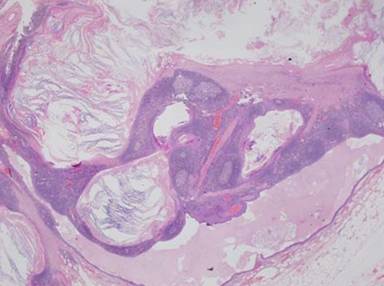

A gross pancreatic lymphoepithelial cyst mass has been described as pink, friable, and filled with keratinous yellowish-white material [13, 28]. Histological examination classically shows a true cyst lined by stratified squamous-type epithelium and surrounded by a dense band of lymphoid tissues with germinal centers [44] (Figure 3). Mucous cells have also been reported in up to 78% of these cysts [6, 13].

|

Figure 3. Microscopic picture of pancreatic lymphoepithelial cyst showing lymphoid nodules with germinal centers outside the cyst’s thin, keratinized epithelial lining. (Reproduced with permission from England and Allen [44]). |